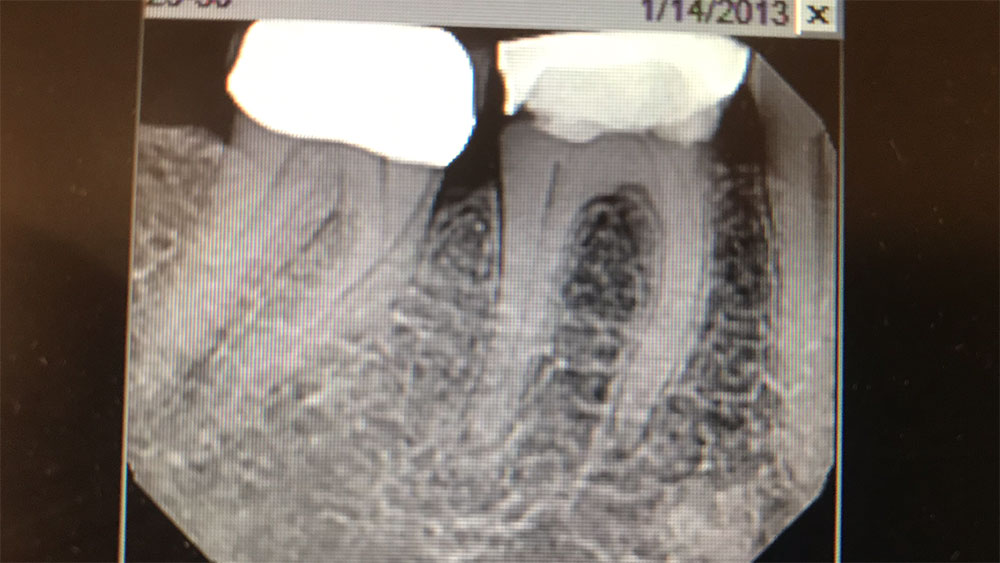

So that first experience was great, but the case I want to share is an interesting two-implant case I recently did to replace a single molar. The tooth could have been restored with a root canal, post and core, and crown, but implant treatment offered a better long-term prognosis and was the patient’s preference after learning of her options. We went with two 3.5 mm x 11.5 mm Hahn implants because the buccal-lingual bone width was too narrow to accommodate a larger implant and placing one implant of that size would have made the crown look like a lollipop. The biomechanics wouldn’t have been great either, so we went with two medium-sized premolars, which also resulted in better hygiene. I extracted the tooth, grafted the socket with Newport Biologics™ Mineralized Cortico/Cancellous Allograft Blend (Glidewell Direct), and placed the implants four months later.